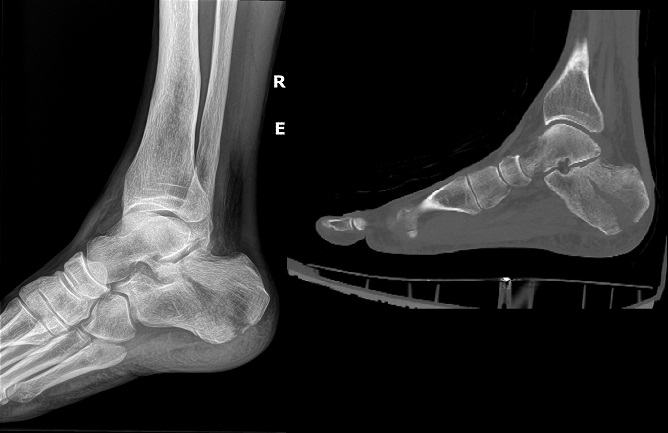

An 80 year old female presents to your office with a left ring finger deformity after a fall one week ago. She initially went to urgent care and xrays were unremarkable for a fracture (Figures 1 and 2). A photo of her left ring finger is shown in figure 3. On physical exam the left ring finger is in hyperextension at the PIP joint and flexion at the DIP joint. She able to flex her PIP joint with full motion. What is the best treatment option?